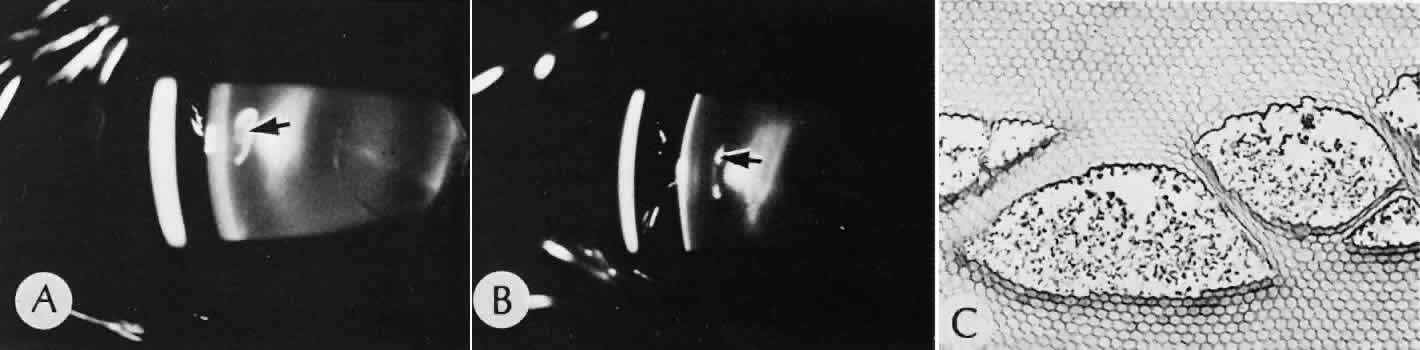

that results in reestablishment of functional ocular anatomy.1–3 The goal of therapeutic intervention in the setting of ocular trauma is to promote the repair process and to allow it to proceed as rapidly as possible and heal as completely as possible without compromising ocular function.4 CELLULAR AND EXTRACELLULAR COMPONENTS The four basic cell types found in wound healing are fibroblasts, vascular endothelial cells, inflammatory cells, and epithelial cells. Specialized cell types that participate in ocular wound healing include corneal endothelial cells, retinal pigment epithelial cells, and Müller cells of the retina. Specific cell populations enter an area of injury under the influence of complex biochemical and biophysical processes involving proteins of the extracellular matrix and the coagulation system. Intracellular proteins, such as tubulin and actin, andmyosin filaments function in cell locomotion. Extracellular matrix proteins, such as fibronectin, laminin, and type IV collagen, orient and regulate cell migration and adhesion.5 Coagulation proteins, such as von Willebrand's factor and plasminogen, alsofunction in regulating the cellular events of healing. Vascular endothelial cells are stimulated to leave their resting state and digest basement membrane, proliferate, migrate, and eventually differentiate under the direction of multiple angiogenic growth factors.6 A wound usually is filled first by a fibrin coagulum. Neutrophils, lymphocytes, and histiocytes (macrophages) enter the wound through fibrin scaffolding to clear necrotic debris and confine toxic or foreign substances. Granulation tissue often is the first type of reparative tissue in wound healing (Fig. 1). Although its composition varies somewhat, small-caliber vascular channels in a delicate collagenous stroma infiltrated by acute and chronic inflammatory cells generally characterize it. This amorphous tissue serves as a template for more definitive repair. Metaplasia is the transformation of a cell from one adult cell phenotype to a second cell phenotype. In advanced wound healing, fibroblasts acquire intracytoplasmic characteristics of smooth muscle cells (myofibroblasts).7 The myofibroblasts are able to contract and bring wound edges together. Vascular endothelial cells proliferate and migrate into the wound from preexisting adjacent vessels. The new “vessel” migrates initially as a solid bulb of endothelial cells. This solid cord of cells will canalize and differentiate into mature arterioles, venules, and capillaries. Fibroblasts grow into the wound in a radial manner but will eventually reorient and secrete collagen along lines of established tissue tension. Epithelial cells are found covering surfaces of tissue. Two distinct types of epithelial cells cover the ocular surface: corneal epithelial cells and conjunctival epithelial cells. Cell replacement is accomplished by stem cells located at the limbus for the corneal epithelium8,9 and at the mucocutaneous junction and possibly throughout the conjunctiva for the conjunctival epithelium.10 Migration and proliferation of surrounding healthy epithelial cells heal surface discontinuity. Apoptosis is a biochemical process leading to programmed cell death. Cell death in apoptosis results from intracellular messages. In necrosis, cell death results from toxic external factors (e.g., hyperosmolality). Apoptosis allows for elimination of entire populations of cells without tissue damage or an inflammatory response.11 Elimination of certain cells is advantageous in embryology (e.g., when scaffolding structures are no longer necessary as with the primary vitreous). In certain neoplastic conditions, however, defects in apoptosis may lead to disadvantageous accumulation of cells. Apoptosis also seems to be highly influential in all types of inflammation, including wound healing. In wound healing, apoptosis may function to control the type and degree of tissue response.12 In the anterior cornea, keratocytes have been observed to undergo apoptosis in response to wounding of the cornea.13,14 Abnormalities of apoptosis may be responsible for such conditions as keloid formation in the skin15 and keratoconus in the cornea.16 Wound healing of highly specialized tissues of the eye has several unique features. CORNEAL HEALING The healing of the cornea is unique relative to other soft tissues, because it lacks blood vessels and because it is lined anteriorly and posteriorly by layers of epithelial-like cells. Epithelial cells of the corneacan produce essential wound healing factors normally produced by platelets.17 Architectural repair is accomplished at the level of the corneal stroma. Abrasions are injuries generally involving only the superficial layer (epithelium) of the cornea (Fig. 2). Abrasions are commonly caused by mechanical injuries or anoxia resulting from contact lens overwear. Some or all of the layers of the surface epithelium are lost, but Bowman's membrane remains intact. After a delay of approximately 1 hour, uninjured epithelial cells at the margin of the wound loosen their intercellular and basal attachments and migrate en masse toward the injured area.18 The shape of the wound margin and the biochemical characteristics of the exposed tissue influence the direction and extent of the migration.19 If the entire corneal epithelium is abraded, migrating epithelial cells derived from the limbal stem cells are able to cover the defect completely within 48 to 72 hours. The epithelium will be much thinner than normal until mitotic division reestablishes normal thickness. Re-formation of epithelial basement membrane may not be detectable for as long as 6 weeks after injury.20 Clinically, the healed wound is transparent. Small defects of Bowman's membrane (Fig. 3) do not heal by fibrous proliferation of the stroma. The defect is filled by proliferating epithelial cells (epithelial facet formation) that reestablish the surface continuity of the cornea. The facet may be seen clinically as a focal, well-demarcated, superficial corneal opacity. A corneal foreign body causes this lesion most often. Penetrating corneal injuries involving at least one third of the stroma (Fig. 4) are covered initially by proliferating surface epithelium that may extend for a considerable distance into the stroma. The extent of corneal epithelial migration is controlled at least in part by contact inhibition of migration once contact with healthy corneal endothelial cells is established.21 Bowman's membrane has elastic properties that tend to pull the anterior margins of the wound apart. Exposure of the relatively dehydrated corneal stroma to tears and blood will cause swelling of the corneal stroma. This swelling of the stroma tends to close the wound. As the stroma heals, new collagen is produced by keratocytes or transformed monocytes. Epithelial cells will regress toward the surface. The repair collagen is different from the native collagen in size and in orientation. The healed wound is densely opaque and obvious clinically, but it may be detected histologically only by the break in Bowman's membrane. Full-thickness wounds of the cornea are associated with retraction of Descemet's membrane and separation of the posterior aspect of the wound (Figs. 5 and 6). Secondary aqueous, a proteinaceous coagulum, may seal the wound posteriorly until healthy surrounding endothelial cells can spread and migrate into the injured area. Mitotic division of the endothelial cells possibly plays an important role in younger patients but probably is not clinically significant in adults. Ultimately, migrated endothelial cells will produce a new Descemet's membrane (Fig. 7).22–25 The portions of Descemet's membrane displaced into the stroma are not resorbed, but remain as the histologic marker of the site of injury. The anterior cellular surface repair of migration and mitosis of epithelial cells is the same as that described for more superficial corneal wounds. The important exception is that with full-thickness injuries, there is a risk of surface epithelial cells migrating along the posterior surface of the cornea or the anterior surface of the iris to the trabecular meshwork. The displaced epithelial cells will cause scarring of the trabecular meshwork and secondary open-angle glaucoma. CONJUNCTIVAL HEALING Conjunctival healing differs from corneal healing because of the presence of blood vessels and a lymphatic system. The conjunctival epithelium heals by migration and mitosis.26 Conjunctival stem cells are thought to originate at the mucocutaneous junction and migrate to the fornix.27 Goblet cells are produced by epithelial progenitors and appear once conjunctival epithelial cell continuity has been reestablished.28,29 The presence of vascular tissue in the substantial propria of the conjunctiva allows for the formation of granulation tissue and scar tissue, as found in soft tissues elsewhere. SCLERAL HEALING The sclera itself does not participate directly in wound healing. Partial-thickness injuries are healed by formation of granulation tissue from the epi-scleral tissue in external wounds or from uveal tissue in internal wounds (Fig. 8). Full-thickness defects of the sclera heal by granulation tissue originating in the episcleral tissue and uveal tract. Mitomycin is used in filtering procedures specifically to prevent the formation of granulation tissue and promote establishment of an aqueous fistula.30 SURGICAL LIMBUS HEALING Currently, there is a trend for the site of the cataract wound to shift from the limbus to the peripheral cornea31 to reduce induced astigmatism32 and to shorten the natural history of cataract wound healing.33 The healing of the wound is similar to that found in central corneal incisions. Healing at the site of a limbal surgical incision involves a combination of the features of repair of the cornea, conjunctiva, and sclera (see Fig. 5). Conjunctival epithelium will heal over an area of granulation tissue originating from the substantia propria of the conjunctiva and the episclera. The granulation tissue seals the wound if the wound edges are well apposed. The remainder of the healing process is similar to the healing of an external scleral wound. Granulation tissue is not formed in the internal portion of the wound because the uveal tract is not involved. The internal wound is healed by endothelial migration and reformation of Descemet's membrane in a manner outlined above for full-thickness corneal wounds.34,35 Because of the lack of blood vessels, the rate of wound healing is slow relative to that of the skin. Whereas an injury to the skin may have regained its tensile strength in 7 to 10 days, injuries to the surgical limbus may require as long as 12 months to regain a stable tensile strength. The tissues of the wound remain structurally weaker than the surrounding uninjured tissue (Fig. 9). The healing of a clear corneal cataract incision proceeds as described above. UVEAL HEALING Wound healing of the posterior uveal tract follows the general principles for healing of vascularized tissue. The iris, however, heals differently. When the iris wound is perpendicular to its circumferential ridges, such as in a typical peripheral iridectomy or iridotomy, the cut edges pull apart. Granulation tissue does not form to close iridectomy incisions probably because of the inhibitory effect of the aqueous flowing through the opening of these small incisions. Iridotomies created by argon laser (Fig. 10) may be anatomically closed by apparent migration of iris pigment epithelium.36,37 LENS HEALING Proliferation and fibrous metaplasia of the lens capsular epithelium (Fig. 11) may close small rents through the lens capsule. After maturation of the fibrous tissue, the most superficial epithelial cells will form a new lens capsule. Most wounds to the lens, small and large, result in cataracts. Small wounds, however, may result in tiny focal opacities.38–39 Lens epithelial cells undergo fibromyoblastictransformation when stimulated by injury. The transformed cells are able to produce type I and type III collagen and glycosaminoglycans.40 This is the fundamental process resulting in opacification of the posterior lens capsule after extracapsular cataract extraction or phacoemulsification.41 Apoptosis (programmed cell death) also plays a role in the formation of secondary cataracts.42 RETINAL HEALING Wound healing of the neurosensory retina follows the principles of wound healing. There is an initial removal of all necrotic tissue by phagocytosis followed by proliferation of cells to form a chorioretinal bond. The healing, however, is modified in most instances by the lack of participation by the blood vessels.43–45 Astrocytes from the neurosensory retinaproliferate from the peripheral viable tissue into the wound and downward into the area of the subretinal space (Fig. 12). Retinal pigment epithelial cells from the peripheral viable tissue undergo fibrous metaplasia and proliferate upward into the area of the subretinal space. When the two proliferating cell types unite, a tight chorioretinal bond is formed. Increased retinal adhesiveness has been estimated to be 140% of the normal degree of adhesiveness 2 weeks after photocoagulation.46 Retinal holes may heal spontaneously if supported by an intact vitreous base or if located adjacent to the retinal pigment epithelium (Fig. 13).47,48 For the retinal pigment epithelium to differentiate, it must be in contact with overlying retinal pigment epithelium.49 Choriocapillaris repair from a photocoagulation wound of the retina appears to proceed in a manner similar to that of repair of capillary thrombosis in other tissues.50 The vascular repair process may not reproduce the lobular architecture of the native choriocapillaris.51 The choriocapillaris may regenerate in areas of restored retinal pigment epithelium.52 Proliferative vitreoretinopathy is an expression of abnormal retinal wound healing.53 Interruption of Bruch's membrane may allow the ingrowth of fibrovascular tissue from the choroid into the subretinal space, resulting in a modified granulation wound healing process and subretinal scarring.54 |